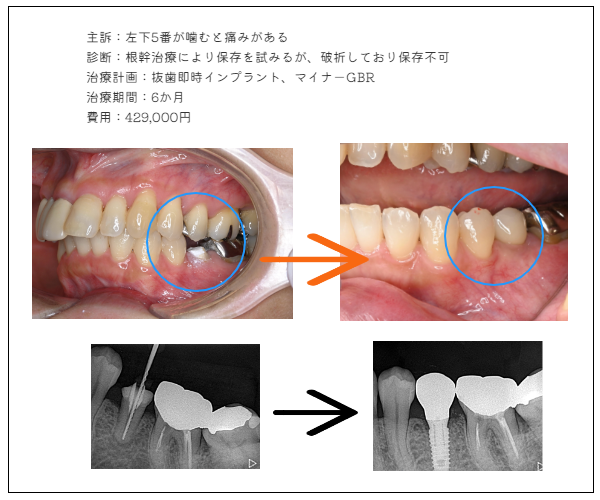

imprant症例4

MYデンタルインプラント